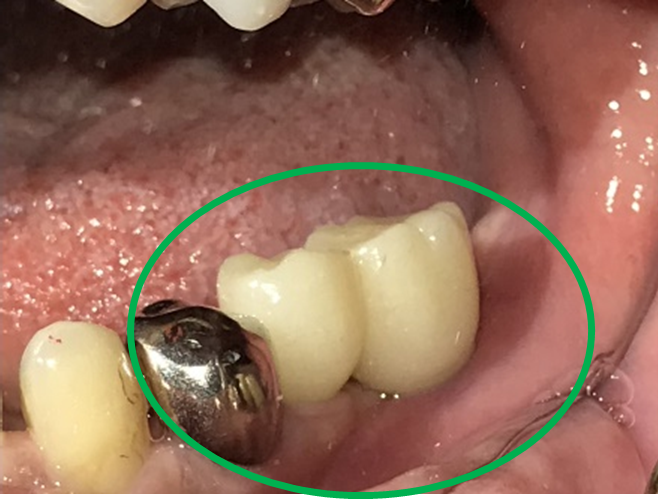

女性Hさん 60代(オールセラミック冠・インプラント)

主訴

右下のブリッジがゆらゆら動く。

治療内容

ブリッジの支台になっている奥の歯が、被せ物の中で虫歯になり、支台の役割を果たさず、前方の歯のみで支えられていました。前方の歯をそのままにして、後方の部分を切り離すと、そのまま取れてきました。中は、虫歯で歯根しか残っていない状況でした。この歯は、根管治療後、単独でオールセラミック冠を被せ、歯のないところにインプラントを埋入しました。

所感

今回の治療法には、次の3つの方法があります。

(1)虫歯になっていた歯の根管治療をし、土台を入れ、また再びブリッジにする。しかし、虫歯になっていたほうの歯は、ブリッジの支台として使うには、心もとなく長持ちしない可能性が高く、今度問題が生じたときには抜歯になる。

(2)虫歯になっていた歯に、単独で被せ物をし、歯のないところに1本だけの部分入れ歯を入れる。取り外しの入れ歯なので、自分の歯のような感覚で噛むことはできない。この方法も歯のない部分の負担を欠損の両側の歯に負担してもらうため、長持ちしない可能性が高い。

(3)虫歯になっていた歯に、単独で被せ物をし、歯のないところにインプラントを埋入する。欠損している部分の負担を前後の歯に負担させないので、歯を守ることができる。また、自分の歯と同じ感覚で食事をすることができる。

患者さんは、3つ目の方法を選択されました。一番長持ちし、これ以上歯を失わないためには、最良の方法だと考えます。

オールセラミック冠(失活歯):¥104,500(税込)

インプラント:¥363,000(税込)

合計:¥467,500(税込)

Before

冠の中で大きな虫歯になり支台の役割を果たしていませんでした。

【インプラント埋入前】

冠はブリッジを切断しただけで取れてきました。軟化象牙質を取り除いたところ、歯根しか残っていない状況で保存できるかどうかのぎりぎりのところでした。

After